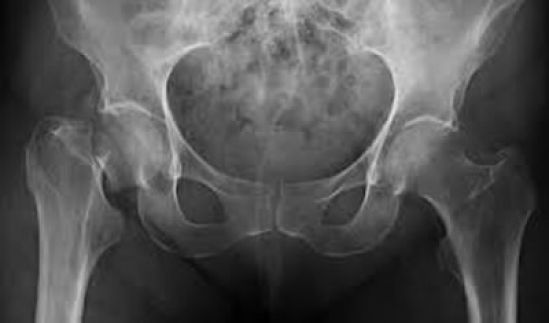

La osteoporosis es conocida como “la epidemia silenciosa”, ya que no tiene síntomas y cada vez afecta a más personas. Se estima que en el mundo se produce una fractura por osteoporosis cada tres segundos3, además, teniendo en cuenta que esta enfermedad causa más de 8.9 millones de fracturas anuales(1) y que en México 3.5 millones de personas mayores de 60 años requieren tratamiento o prevención para este padecimiento(2) se considera ésta una iniciativa necesaria.

Asimismo, se debe tener en cuenta que los antecedentes de haber sufrido una fractura por fragilidad predisponen al paciente a un riesgo considerable de sufrir fracturas futuras; lo que ilustra la gran necesidad de implementar estrategias de prevención para fracturas secundarias.

Actualmente, existen terapias que ayudan a controlar la pérdida ósea y refuerzan los huesos para evitar posibles fracturas, sin embargo no existe una cura para la osteoporosis. Existen diversas opciones de tratamiento como tabletas, parches o inyecciones (4, 5, 6). Amgen ha desarrollado Denosumab, una terapia biotecnológica que se inyecta de manera subcutánea dos veces al año, lo que permite un mayor apego al tratamiento, que ayuda a incrementar la densidad mineral ósea y reducir la incidencia de fracturas de cadera, vertebrales y no vertebrales.